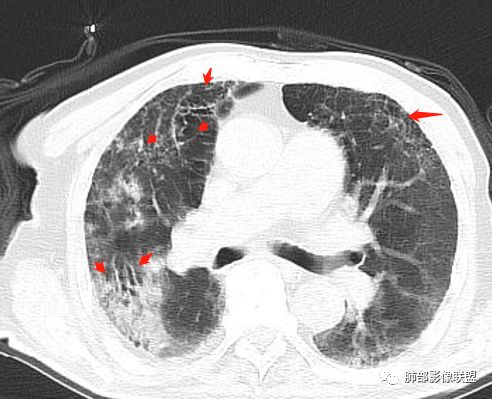

右肺上叶大片实变,其内可见虫蚀样空洞及扩张支气管,其中一空洞内可见曲菌球样结构,右肺体积略缩小。老年糖尿病患者,慢阻肺背景,考虑右肺上叶干酪性肺炎并曲霉感染。

老年糖尿病患者,右肺上叶大片状阴影,内见不规则空洞,内见结节,支气管壁增厚,其他肺野可见气囊影,考虑感染性病变,糖尿病患者常见的四大金刚(金毛结克),金黄色葡萄球菌感染,虽然有气囊,但是临床和其他影像不支持,毛霉菌感染,临床症状重,影像可见液平面,也不支持,肺克临床和影像表现不支持,考虑结核,待排结核合并曲霉菌感染。

右肺上叶大片实变并散在空洞影,洞壁光滑,张力低,部分实变内可见支气管走形,双下肺散在纤维索条及渗出影,纵隔及肺门淋巴结肿大伴钙化,病史有糖尿病,考虑结核,鉴别:肺克,奴卡,毛霉

老年男性,糖尿病患者,右上肺大片实变,内可见多发虫蚀样空洞,右尖段近胸膜处一空洞内可见一类圆形结节影,支气管扩张,淋巴结肿大,双下肺索条,胸膜增厚。结合糖尿病病史,首选考虑结核干酪性肺炎合并曲霉菌感染,待排肺炎型肺癌

老年男性,糖尿病基础,有咳嗽,喘累症状,病程10天,右上肺大片实变,内虫嗜样,无壁空洞,支气管壁增厚,扩张,淋巴结肿大,胸膜增厚,考虑干酪性肺炎,鉴别粘液腺癌。

老年男性,糖尿病病史,慢性病程,右胸廓塌陷,右肺沿支气管分布实变及GGO,叶段分布趋势,其内见支气管充气征及虫蚀样空洞,周围间质受累,指向气道来源病变播散,纵隔淋巴结肿大,密度高伴钙化,综合考虑干酪性肺炎。鉴别肺炎型肺癌。

老年男性,有糖尿病史,右肺上叶大片实变影,有支气管充气征,支气管走行僵直,有扩张,有多发无壁小空洞和俩个稍大空洞,胸膜稍增厚,双下肺野间质性改变,考虑肺结核,干酪性肺炎可能性大。

老年男性,右肺上叶大片实变,边界局部清楚,局部模糊,其内见支气管充气征及多发大小不等的小泡状及分枝状无壁空洞。双肺下叶磨玻璃样间质性改变。综合考虑右肺上叶结核,干酪性肺炎可能。

支气管、内部的小囊腔,部分无壁小空洞,病灶部分边界偏清,支持结核